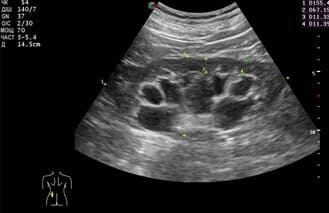

- Разбира се. Първият случай е свързан с камъни в бъбреците. С мен се свърза 27-годишен мъж с болка в дясната страна която започва от гърдите и завършва някъде в областта на пикочния мехур. Болката се проявяваше с кратки спазми, конвулсии, студена пот и се появяваше на вълни. Изображението показва наличието на 19 мм камък, заседнал в горната част на бъбрека. Предписахме Nefro Aktiv . за разбиване на камъни в бъбреците. В рамките на два дни от използването му камъкът започна да се чупи и излезе напълно за една седмица. Пациентът не чувства дискомфорт.